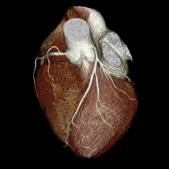

狭心症や心筋梗塞などの虚血性心疾患は年々増加傾向にあり、現在国内死亡原因は癌に次ぎ第2位となっております。心臓CTはマルチスライスCTという装置を用いて心臓を撮影し、コンピュータ処理し3次元画像を含む様々な方向から心臓を診断する手法です。 心臓は体内でも動きが活発な臓器の一つで静止画撮像が難しい分野でした。しかし近年の画像診断技術の進歩により、これまで主に入院での冠動脈造影などの心臓カテーテル検査で評価されていた冠動脈病変や心筋症の診断が外来CTでも可能となりました。

当院では64列マルチスライスCT(Aquilion ( 東芝メディカルシステムズ社製)で年間約150例の検査を施行しております。また2012年4月から同社の最新式の320列CT(Aquilion One)が導入され、従来よりも被爆量が最大1/5少なく、撮影時間は0.35秒と短く、 造影剤の量が半分以下での検査が可能となりました。当院ではこれらの装置と最新の画像解析ワークステーションを活用して、 先進医療も含めた循環器画像検査を積極的に行っております。

正常冠動脈